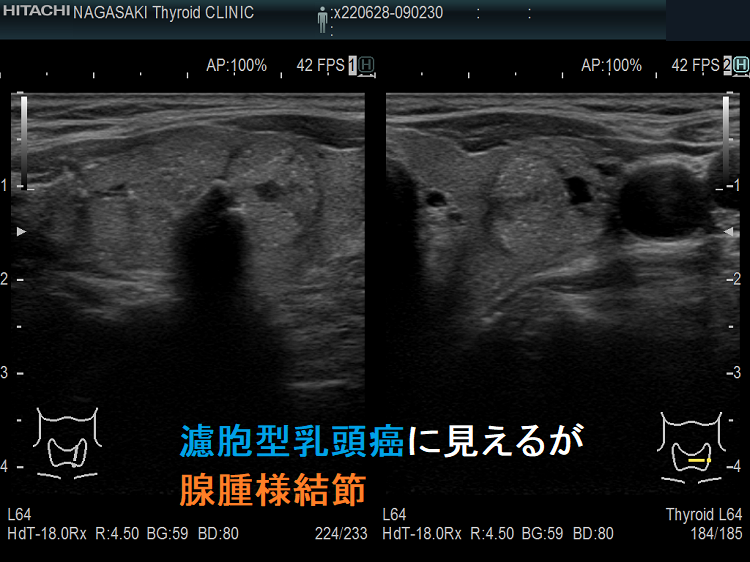

通常のBモード画像では、甲状腺乳頭癌との鑑別が難しいが、エラストグラフィーでは軟らかく(緑)、穿刺細胞診でも腺腫様結節だった。

濾胞型乳頭癌に見えるが腺腫様結節

等エコー、辺縁不整で粗雑、微細石灰化が著明で濾胞型甲状腺乳頭癌が疑われます。

濾胞型乳頭癌に見えるが腺腫様結節 エラストグラフィー

エラストグラフィーではJTEC パターン1、に見え、濾胞型甲状腺乳頭癌ではなくて腺腫様結節でした。